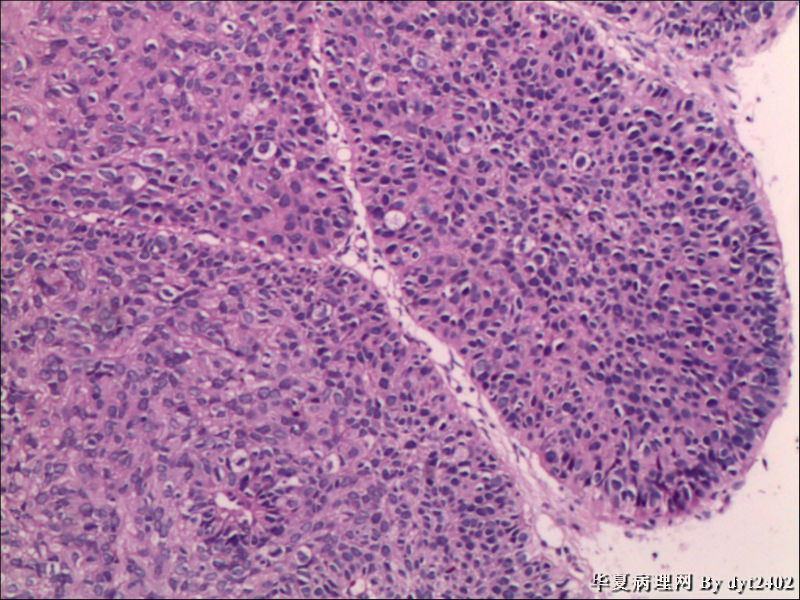

• 宫颈活检 其中一点较迷糊图2

图2

四点中三点是CIN iii,另一点怀疑有更重病变

这个病人是44岁,去年11月底阴道脱落细胞、TCT均见细胞异常,建议活检,病人犹豫,接着单位组织到外院体检时做阴道镜正常,后霉菌感染,此时宫颈未涂醋肉眼看还光滑,直至今年3月来做活检,事前做白带检查又见异常细胞,宫颈未涂醋见后上唇白上皮,涂醋酸后上下唇都有厚白上皮,镶嵌,夹活时上皮剥脱,未能夹到间质,阴道镜医生说至少有CIN III 到原位癌了。。镜下其中3点CIN III无疑,唯有9点处如6、7、11、14等所示结构,但我未见间质浸润,不能说是浸润癌,不知道有没基底细胞样鳞癌的可能,我发了个原位癌不除外深部有更重病变,。